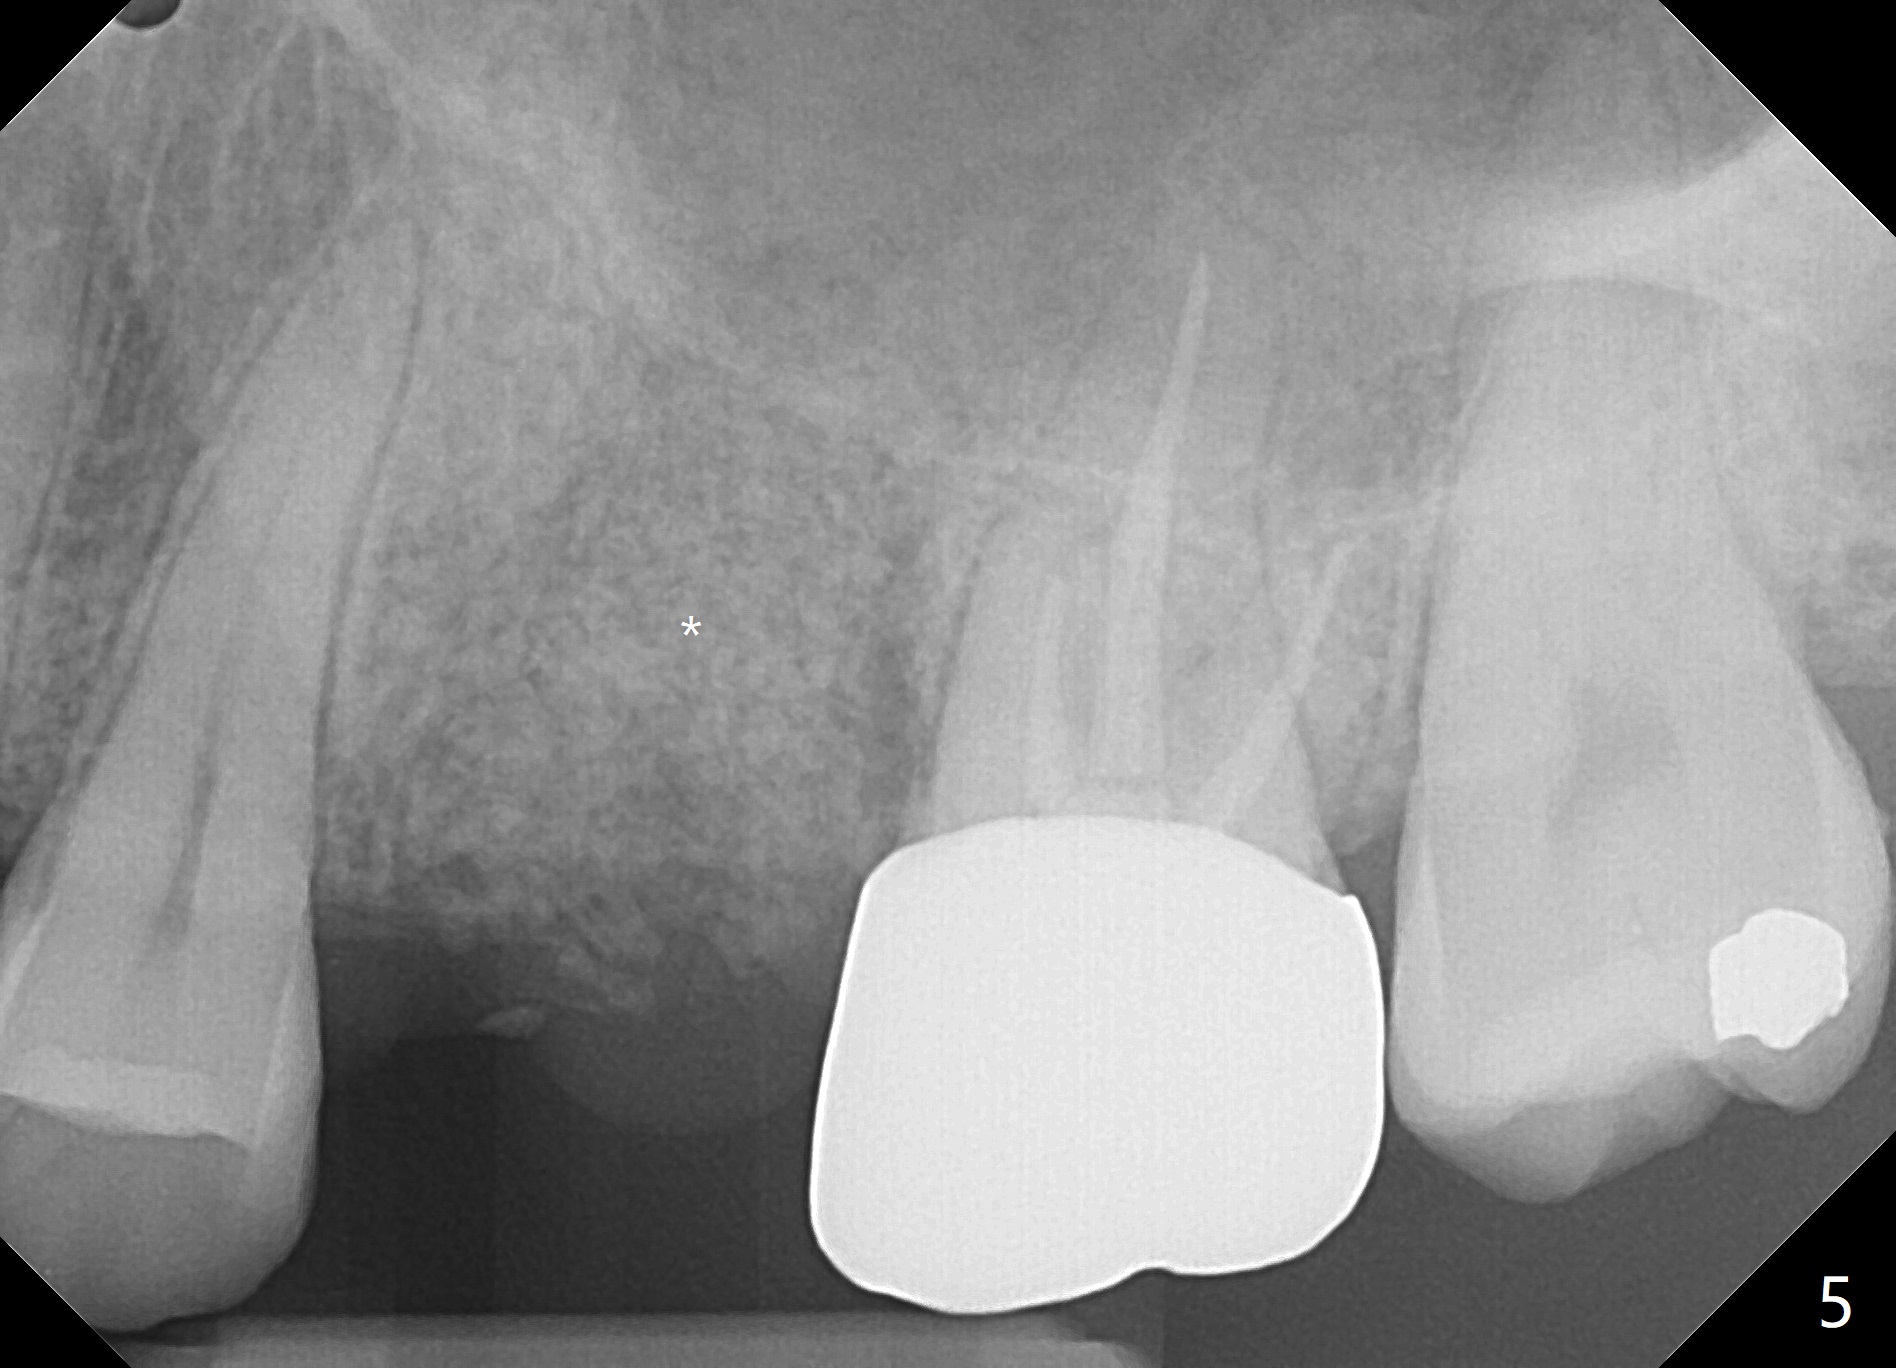

A 42-year-old woman requests extraction of the upper left 2nd primary molar with abscess (Fig.1,3,4). To avoid implants (for #30 as well in Fig.2) and improves cosmetics (anterior crowding), she chooses orthodontics with extraction of 2 more teeth in the other 2 quadrants. It seems necessary to have socket preservation so that the neighboring teeth have the bone to move to (Fig.5 without buccal plate collapse). In fact the coronal half of the buccal plate is resorbed. The bone regeneration is also important in case she changes her mind and ends up needing an implant. Return to Trajectory Xin Wei, DDS, PhD, MS 1st edition 05/17/2019, last revision 05/19/2019